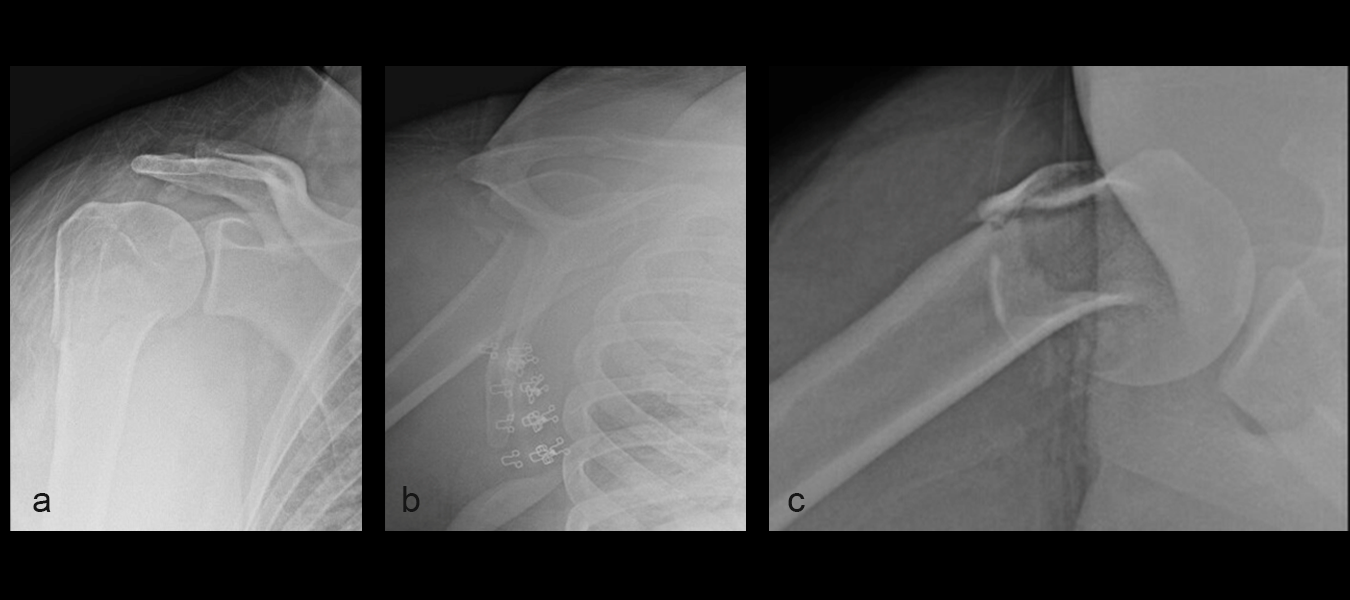

The patient was treated with open reduction and internal fixation (ORIF). First, the fracture was reduced (Fig 2a-b). There was an attempt at closed reduction with continued displacement. Then an open reduction through a deltopectoral approach was performed. After direct reduction, a 1.6 mm K wire was placed along the anterolateral humeral surface. The provisional plate placement and reduction are depicted in Fig 3.

Definitive fixation was performed with a 3-hole VOLT™ Proximal Humerus plate (Fig 4). The plate was placed just beneath the rotator cuff insertion to directly support the greater tuberosity component. The proximal screws angulated toward the superior head to maximize length. The calcar screws were placed in a slightly splayed trajectory. One of the angular stable variable angled screws in the central portion was angulated in a posterior and more central position. This permitted maximal screw spread within the humeral head.